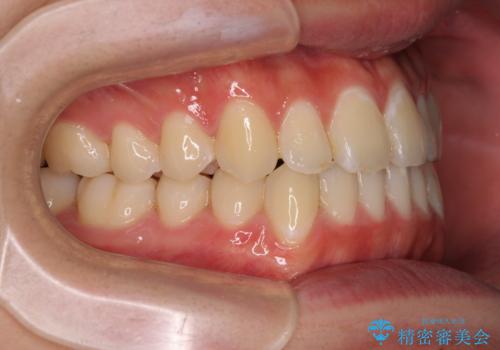

受け口傾向の咬み合わせ インビザラインできれいな口元に

- 前歯のデコボコを治したいとのことで来院された患者様です。

受け口傾向の骨格であり、前歯はクロスバイトまたは切端咬合となっており、叢生は警備であったため、下顎を中心に歯列全体の後方移動を行い、IPR(歯と歯の間を削る)によってデコボコが解消するように設計し、インビザラインにより治療を行うこととしました。

受け口傾向のインビザライン矯正は比較的治療を行いやすいため、きれいに仕上げることができました。舌の突出癖が顕著であったため、改善のためのトレーニングをしっかりと行っていただきました。